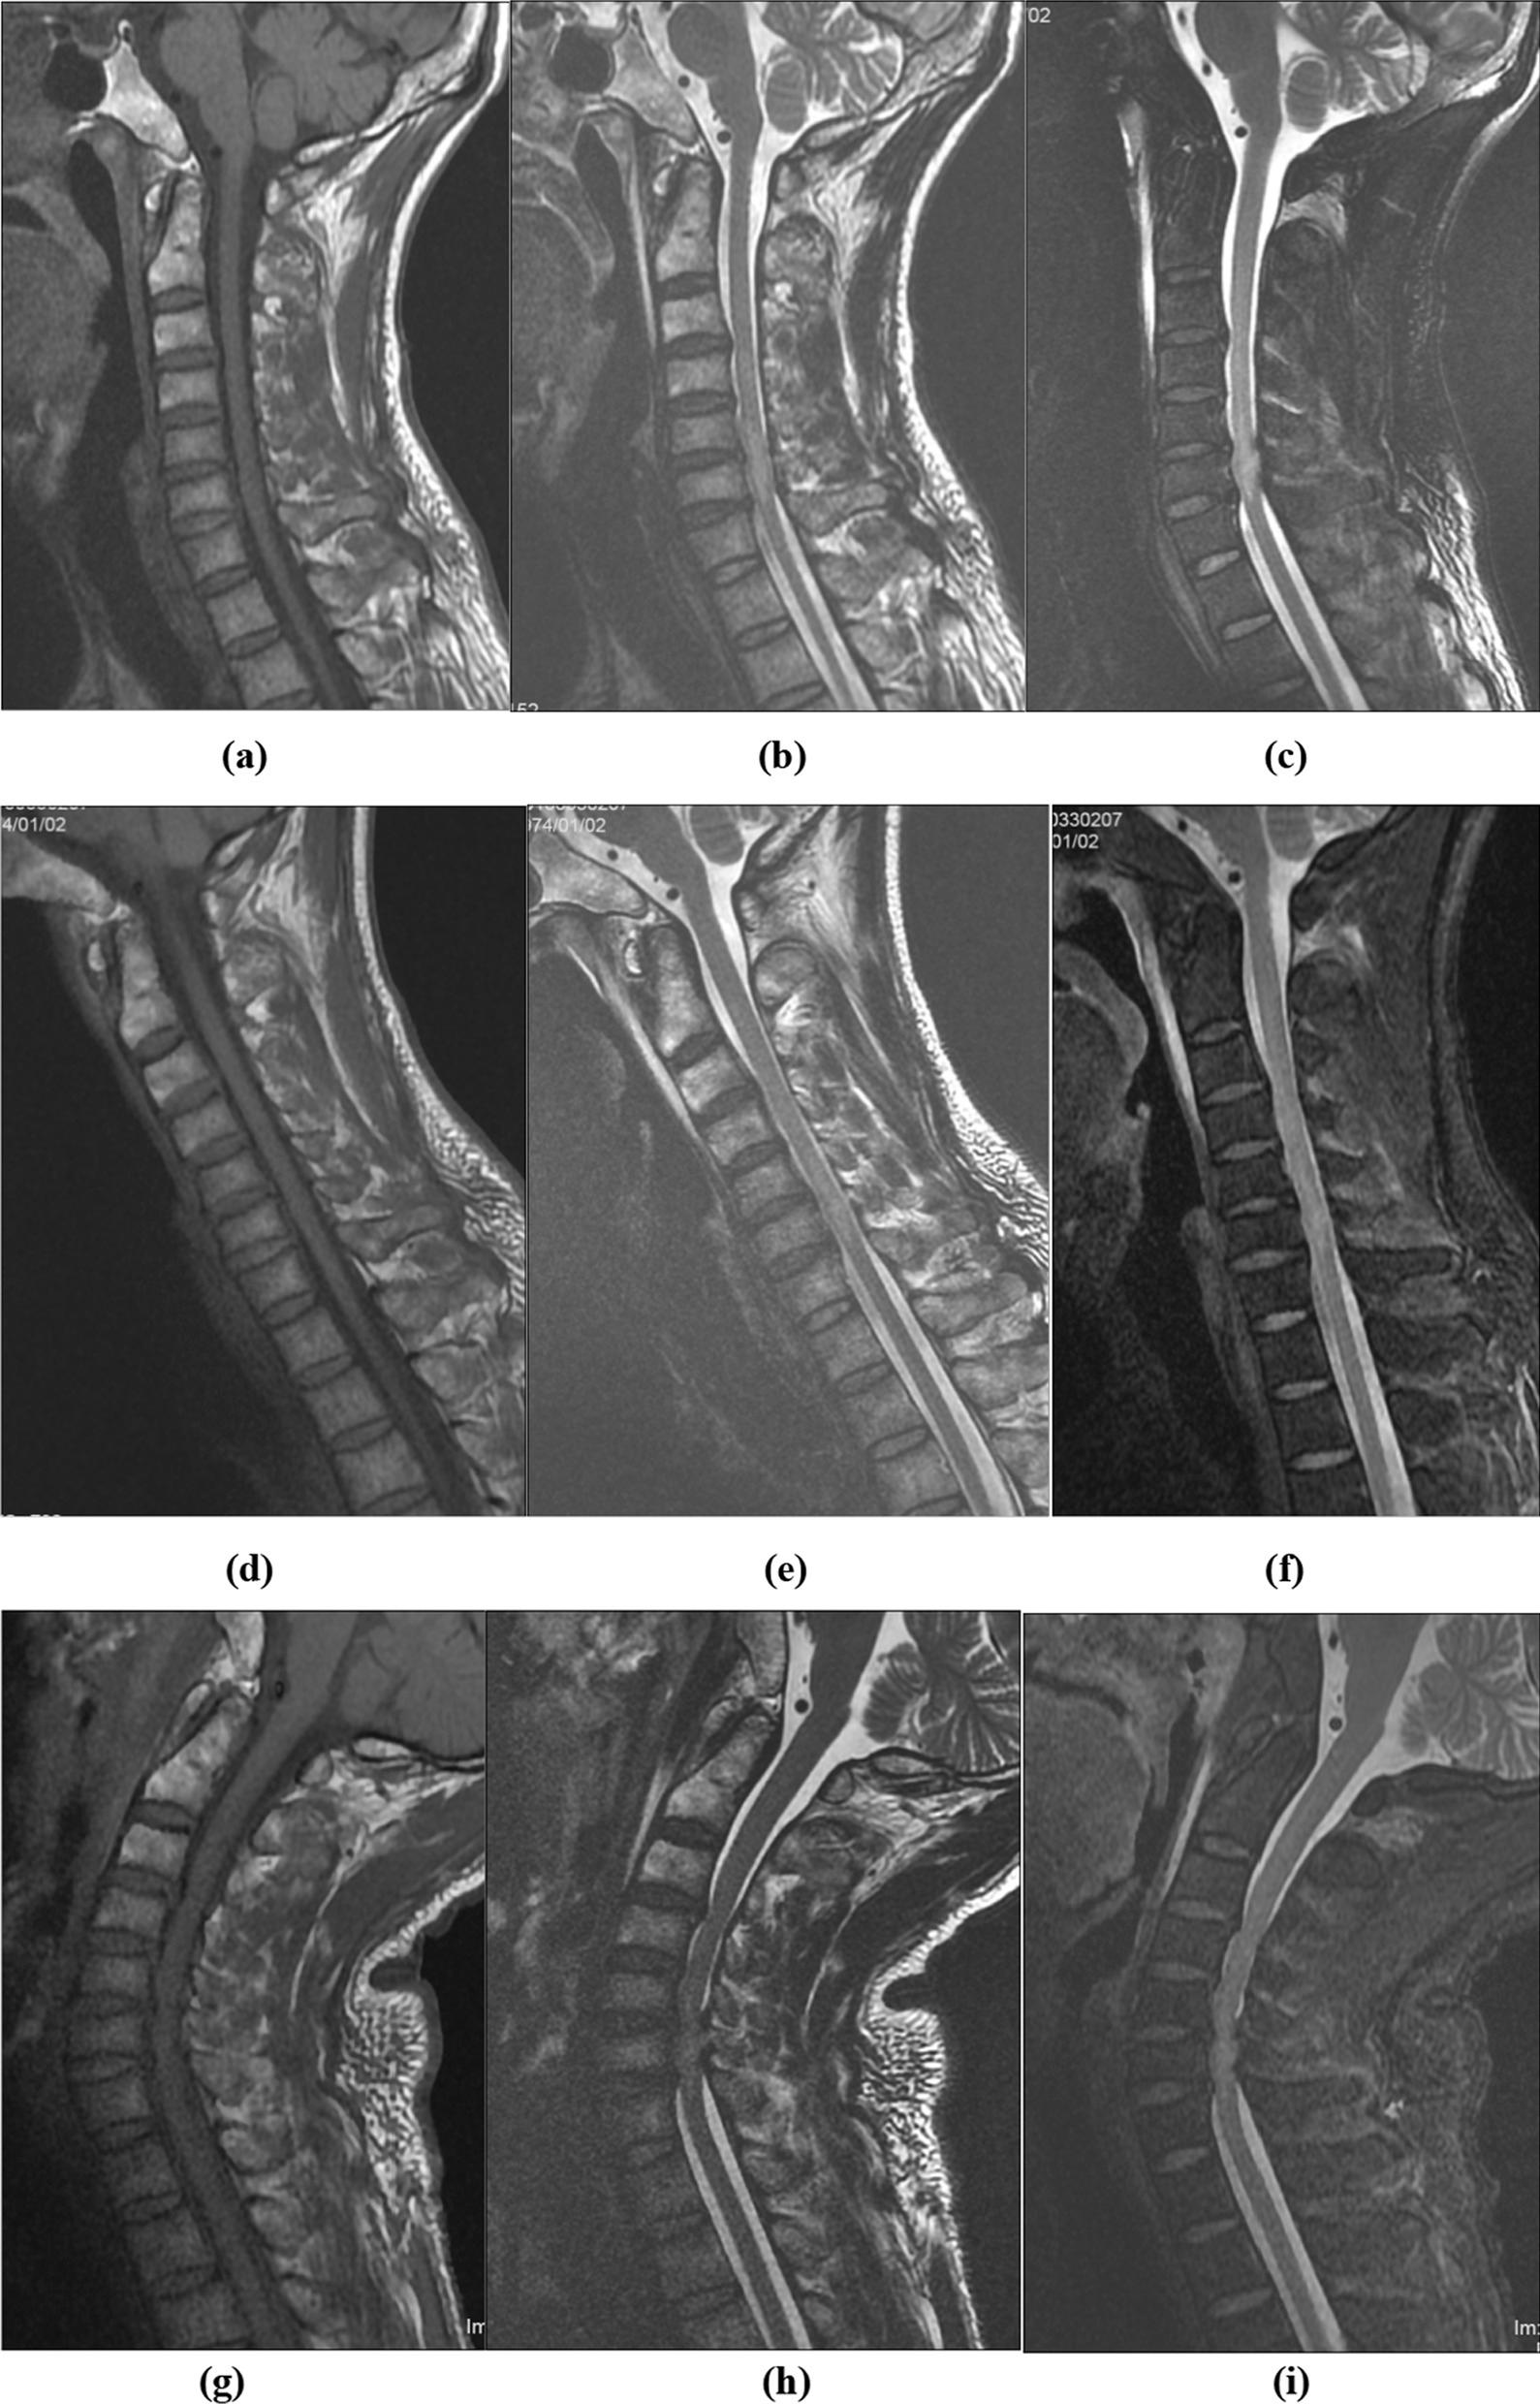

The pattern of changes in the cervical spine and the spinal cord and their dynamic characteristics in patients with cervical spinal cord injury without fracture and dislocation remain unclear. This study aimed to evaluate the dynamic changes in the cervical spine and spinal cord from C2/3 to C7/T1 in different positions by using kinematic magnetic resonance imaging in patients with cervical spinal cord injury without fracture and dislocation. This study was approved by the ethics committee of Yuebei People's Hospital.

Using median sagittal T2-weighted images for 16 patients with cervical spinal cord injury without fracture and dislocation who underwent cervical kinematic MRI, the anterior space available for the cord, spinal cord diameter, posterior space available for the cord from C2/3 to C7/T1, and Muhle's grade were determined. The spinal canal diameter was calculated by adding the anterior space available for the cord, spinal cord diameter, and posterior space available for the cord.

Kinematic MRI demonstrated dynamic pathoanatomical changes, such as canal stenosis in different positions, in patients with cervical spinal cord injury without fracture and dislocation. The injured segment had a small canal diameter, high Muhle's grade, low space available for the cord, and high spinal cord diameter/spinal canal diameter ratio.